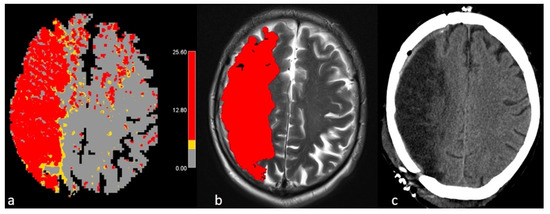

2.7. Postprocessing with FASTER

2.8. Data Comparison

- Infarct core volume: The predicted infarct volume at baseline using FASTER was compared to the final infarct volume on follow-up imaging (MRI or CT) calculated with the slicer.

- Penumbral volume: The estimated penumbral volume by FASTER was compared to the manually delineated volume by Olea using the linear threshold of Tmax (>6 s).